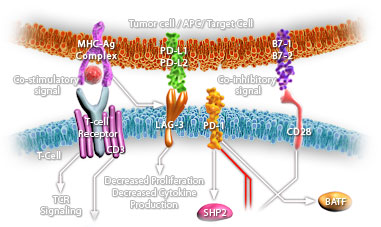

This MAb recognizes a 21kDa protein, identified as the p21WAF1 tumor suppressor protein. This MAb is highly specific to p21 and shows no cross-reaction with other closely related mitotic inhibitors. p21WAF1 is a specific inhibitor of cdk s and a tumor suppressor involved in the pathogenesis of a variety of malignancies. The expression of this gene acts as an inhibitor of the cell cycle during G1 phase and is tightly controlled by the tumor suppressor protein p53. Its expression is induced by the wild type, but not mutant, p53 suppressor protein. Normal cells generally display a rather intense nuclear p21 expression. Loss of p21 expression has been reported in many carcinomas (gastric carcinoma, non-small cell lung carcinoma, thyroid carcinoma).